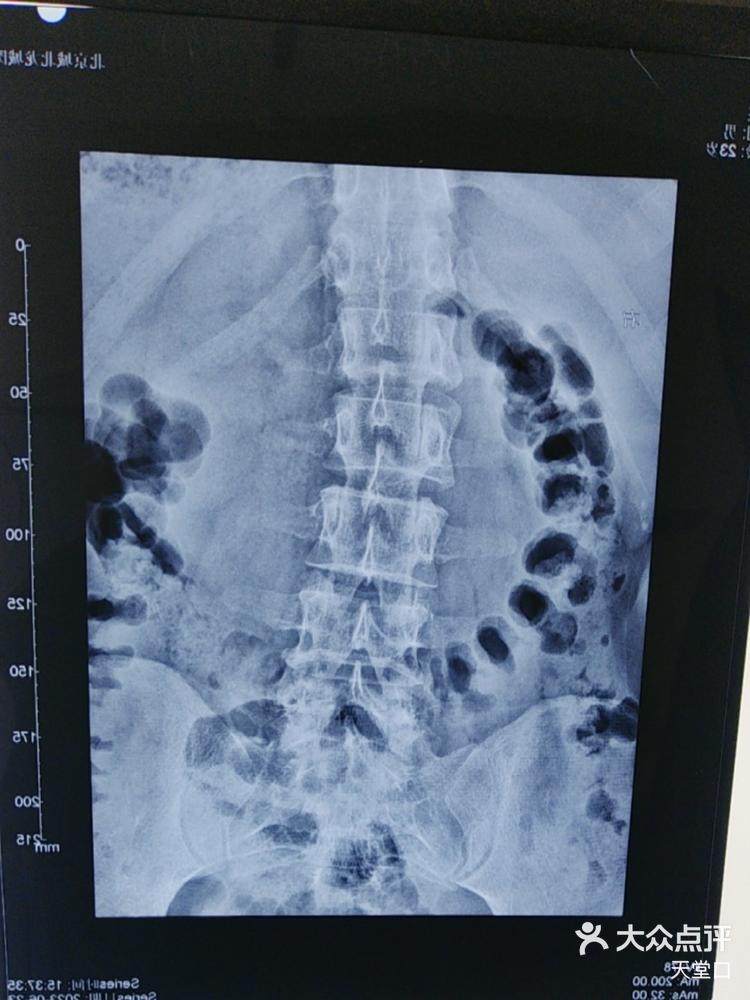

腰椎侧弯

图片尺寸750x1000